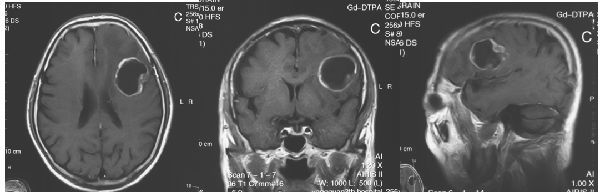

患者为老年男性,因“头痛伴言语不清2周”入院。神经功能障碍主要表现为运动性失语。术前头颅MRI提示:左侧额下回运动性语言功能区的囊性占位,呈环形强化,周边有广泛水肿,左侧侧脑室轻度受压。

术后3天复查MRI,无肿瘤残余。